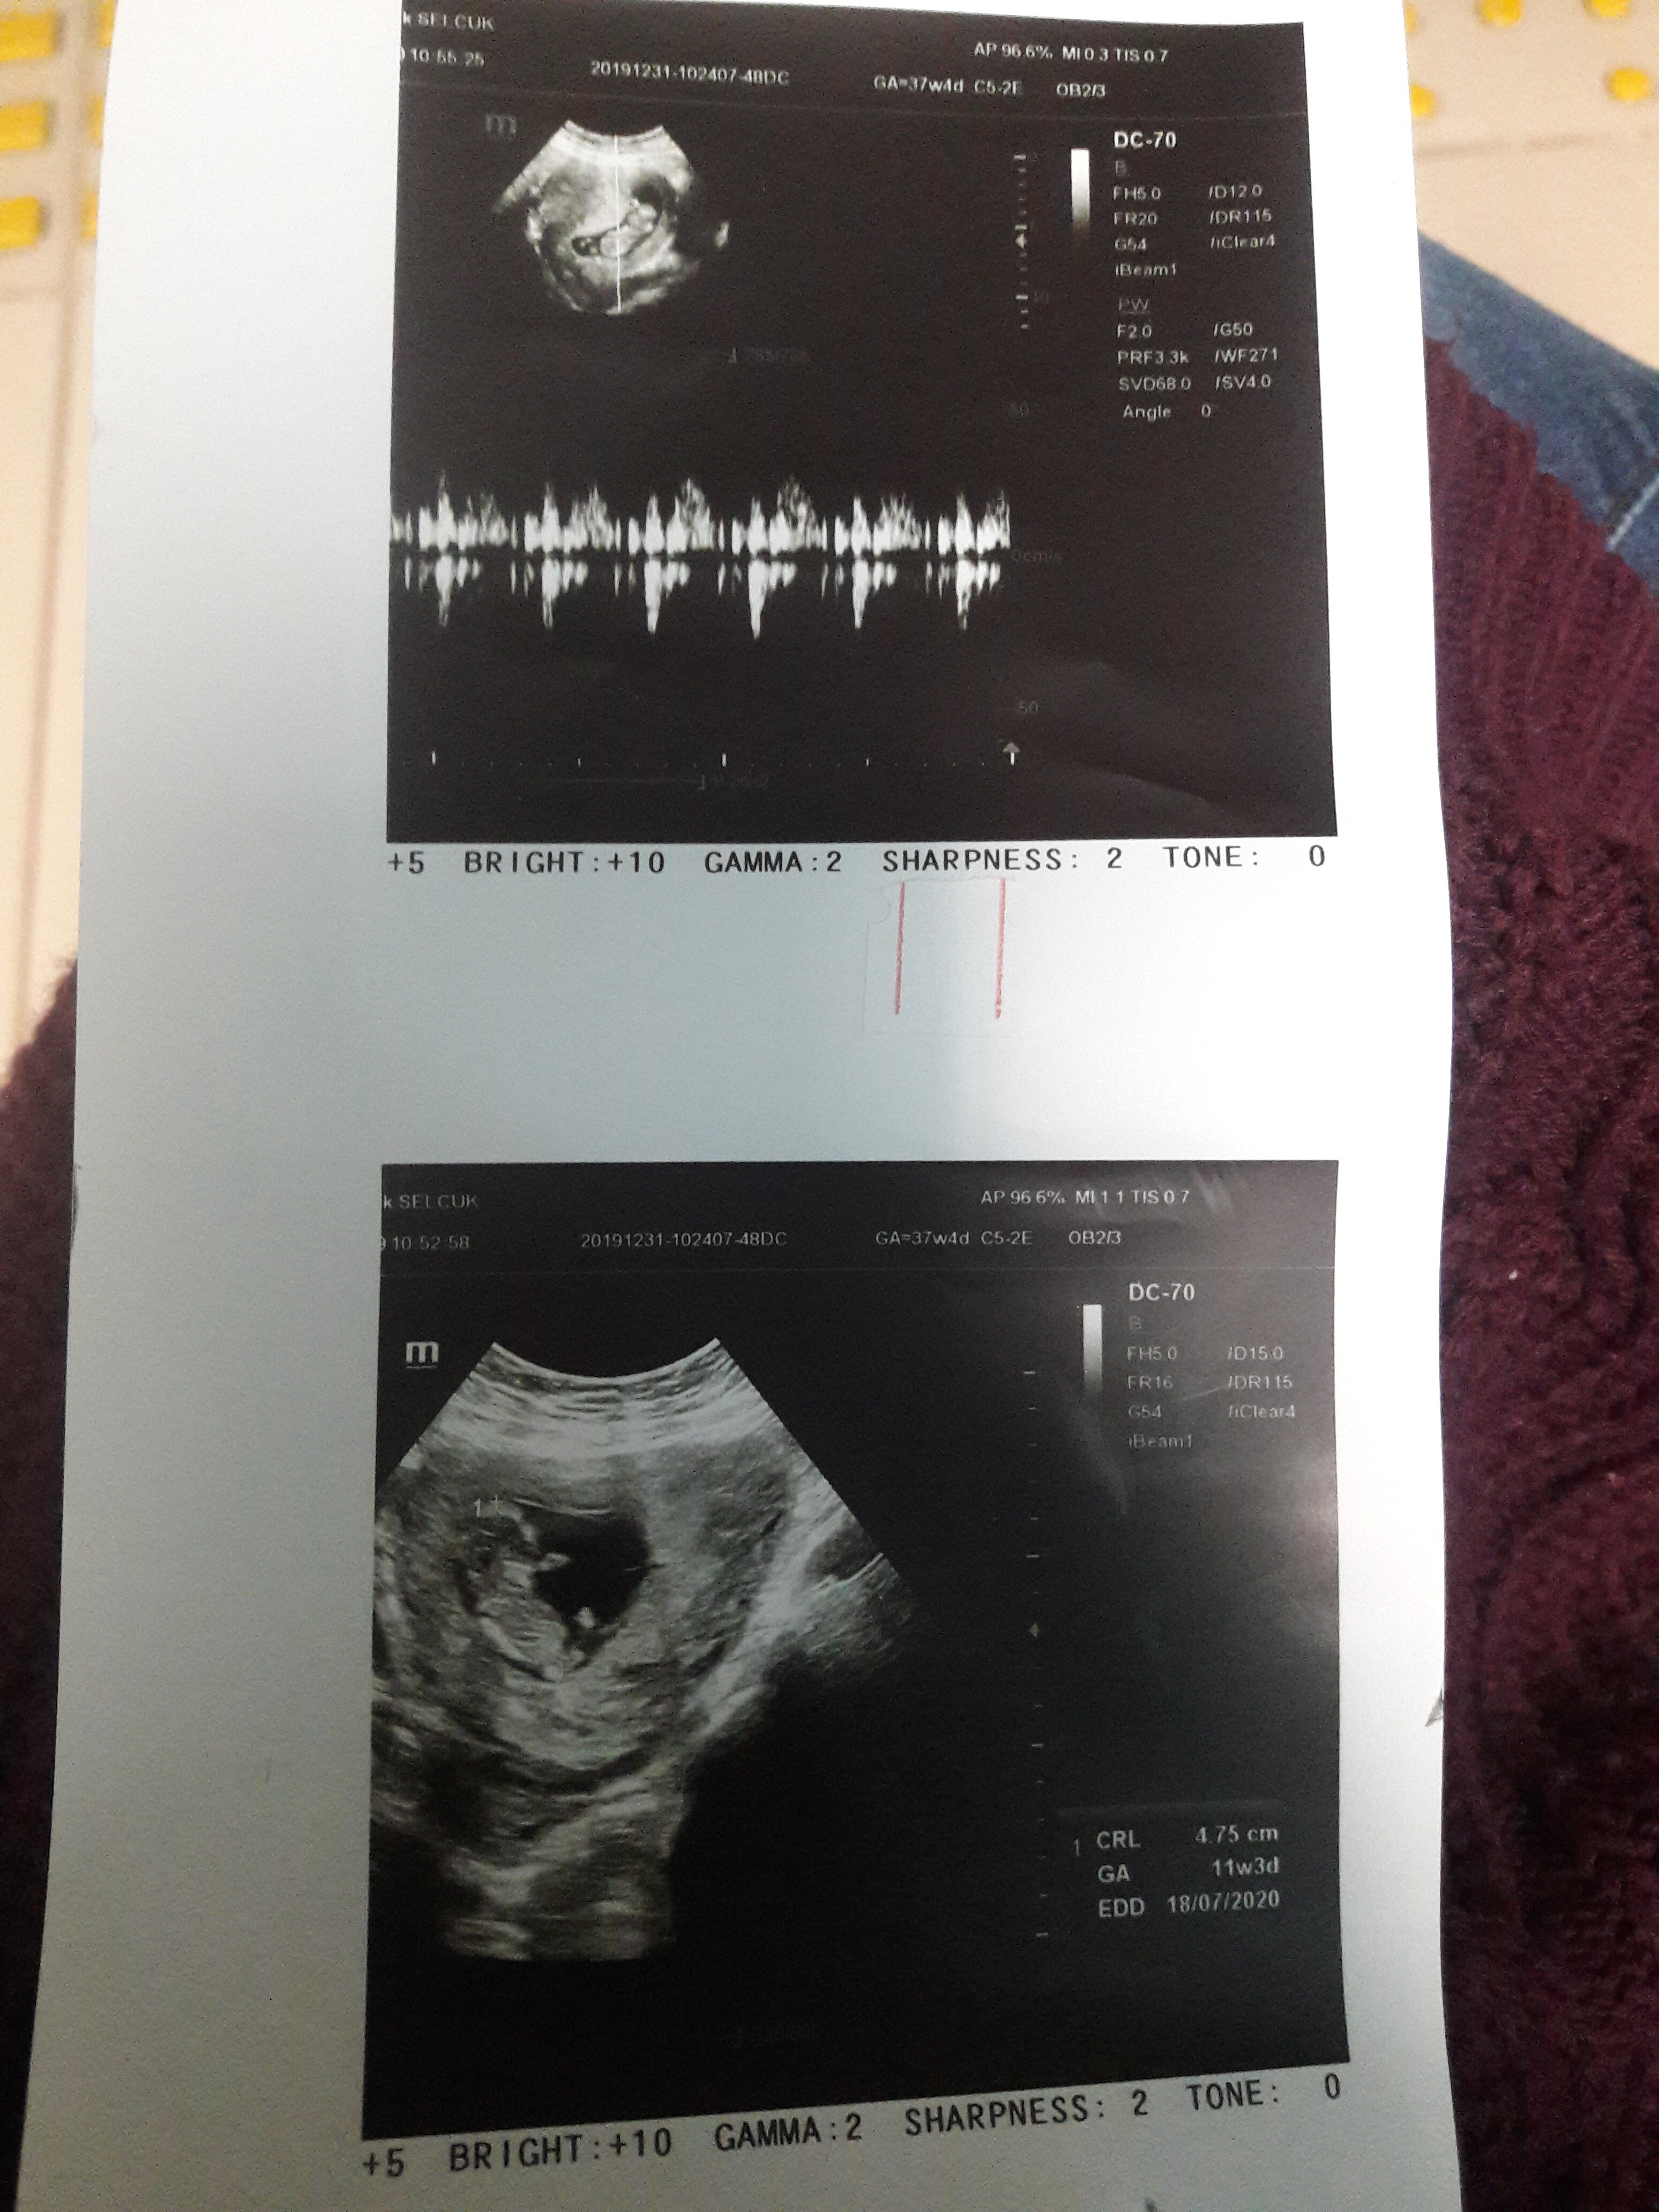

Sümbül 63 Yeni Üye Üye 1 Ocak 2020 #688 Cinsiyet nedir sizce 11+3 Ekli dosyalar 20191231_104945.jpg 1,5 MB · Görüntüleme: 388